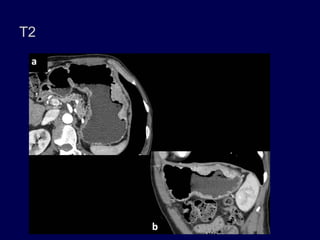

Estadio II. Engrosamiento de la pared mayor

de 1 cm e invade la submucosa y la

muscularis propia. (b) Imagen axial muestra

una masa en el cuerpo inferior, ulcerativa,

focal, transmural con realce sin extensión

perigástrica.

T2